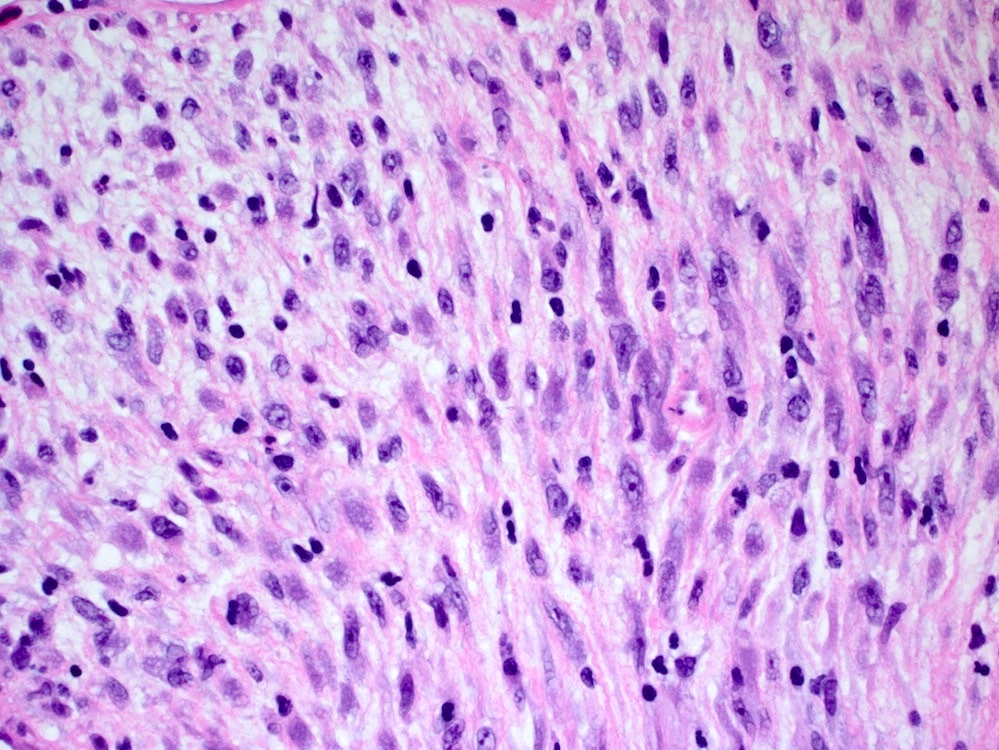

Microscopic (histologic) description

- Bland spindle cells with abundant amphophilic cytoplasm and variably prominent nucleoli

- Lymphoplasmacytic infiltrate with polyclonal plasma cells

- Background may show myxoid change or laminated / whorled fibrosis

- Epithelioid inflammatory myofibroblastic sarcoma: similar, except cells are more epithelioid, with large nucleoli

Microscopic (histologic) images

Contributed by Raul S. Gonzalez, M.D.